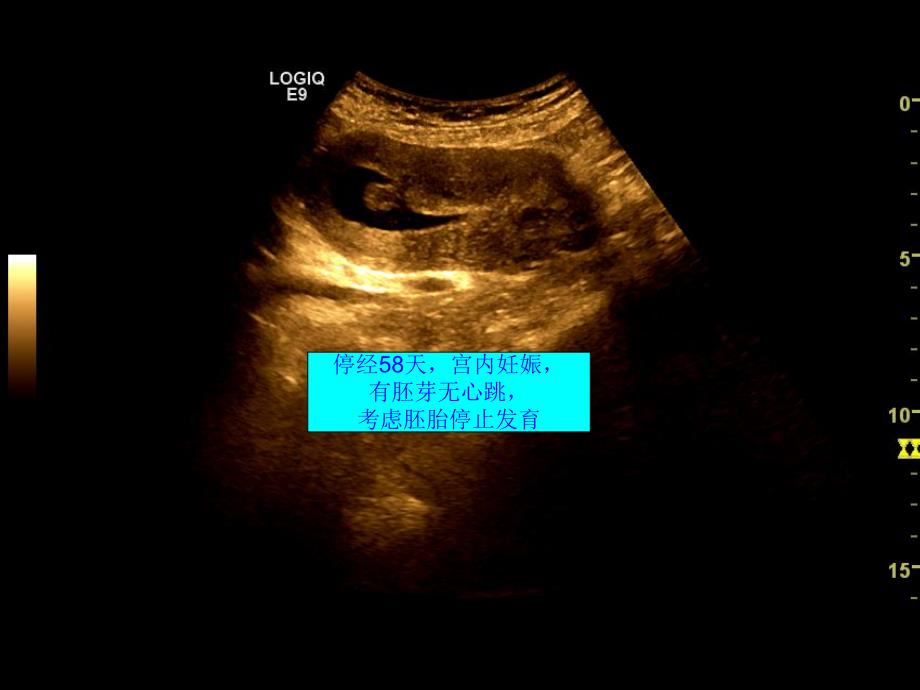

1、子宫切口妊娠的超声诊断 女,30岁,停经58天,阴道不规则少量出血。5年前有破宫产病史。停经58天,宫内妊娠,有胚芽无心跳,考虑胚胎停止发育 人工流产术,患者出现大出血清宫后出现大出血宫腔内积液、下段及宫颈内混合性包块子宫前壁下段回声不均匀06.18 怀疑子宫切口妊娠 对症治疗,一周后复查彩超宫腔仍可见积血。子宫前壁下段、宫颈内口上方可见一包块06.25团块与子宫前壁见可见丰富血流信号,团块内未见明显血流信号06.25频谱为滋养血流 确诊子宫切口妊娠 临床进行甲氨蝶呤(MTX)等化疗治疗 近一月后复查彩超化疗治疗近一月后,包块明显缩小,CDFI少许点状血流信号。07.20二个月后复查,包块消失